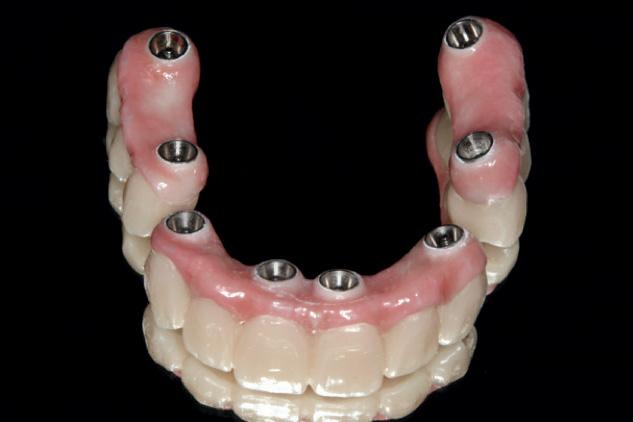

Another common situation is a full mouth restoration over implant. It is well known that the big issue is chipping and delimitation of the ceramics, due to the high forces applied in the patient with dental implants.

In regards to this problem, the combination of rigid materials to support the connectors and resilient materials to absorb the shock and, at the same time, allow easy fixation, make the use of resin based blocks the logical choice for this kind of restoration. (Fig. 6,7 and 8)

A combination of a rigid metal structure over the telescopic bar and a thimble structure made of PEEK (Fig. 13,14) works as base for the final restorations.

In this case, a patient presented with extremely atrophic bone in the mandible, with four short implants placed between the dental nerve foramen (Fig, 10a,10b). These were milled out of a BRILLIANT Crios disc either as single tooth units or bridges and cemented on the thimble struc-ture (Fig. 15-17). Using BRILLIANT Crios instead of prefabricated teeth, we can increase the strength of the restoration, have good aesthetics and keep the weight low for this kind of prosthesis.

After some time, patients wearing this kind of restoration with prefabricated teeth, their muscle activity increase considerably, which very often leads to fracture or debonding of the prefab-ricated teeth (Fig. 12).